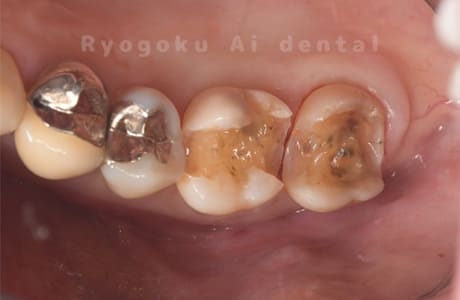

Case11

-

- 原因

- インレー2次カリエス、ならびにインレー脱離

- 治療内容

- セラミッククラウン、セラミックインレー

- 治療費用

- 123,000円×2(セラミッククラン)、77,000円(セラミックインレー)

銀歯が取れて、ご来院された患者様です。奥歯2本をセラミッククラウン、手前の小臼歯をセラミックインレーで治療を行いました。

<リスク・副作用>

過度の咬合や衝撃で割れることがあります。